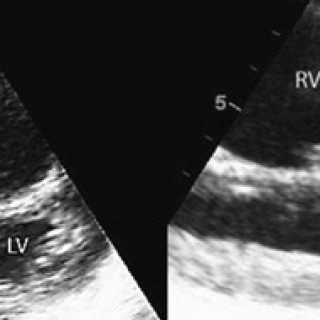

Akutt sirkulasjonsstans er utfordrende både diagnostisk og terapeutisk. Vi presenterer her en kasuistikk som omhandler en ung dyspneisk pasient som utviklet sirkulasjonsstans, med behov for langvarig resuscitering og med liten nytte av medikamentell behandling. I forløpet ble det utført både akutt kirurgi og terapeutisk hypotermi. En 20 år gammel kvinne besvimte på stasjonen etter en cirka to timers togreise. I akuttmottaket var hun blek, satt høyt på båren, var uttalt motorisk urolig, dyspneisk og klaget over brystsmerter. Systolisk blodtrykk var 140 mm Hg, puls regelmessig ca. 80 slag/min og...